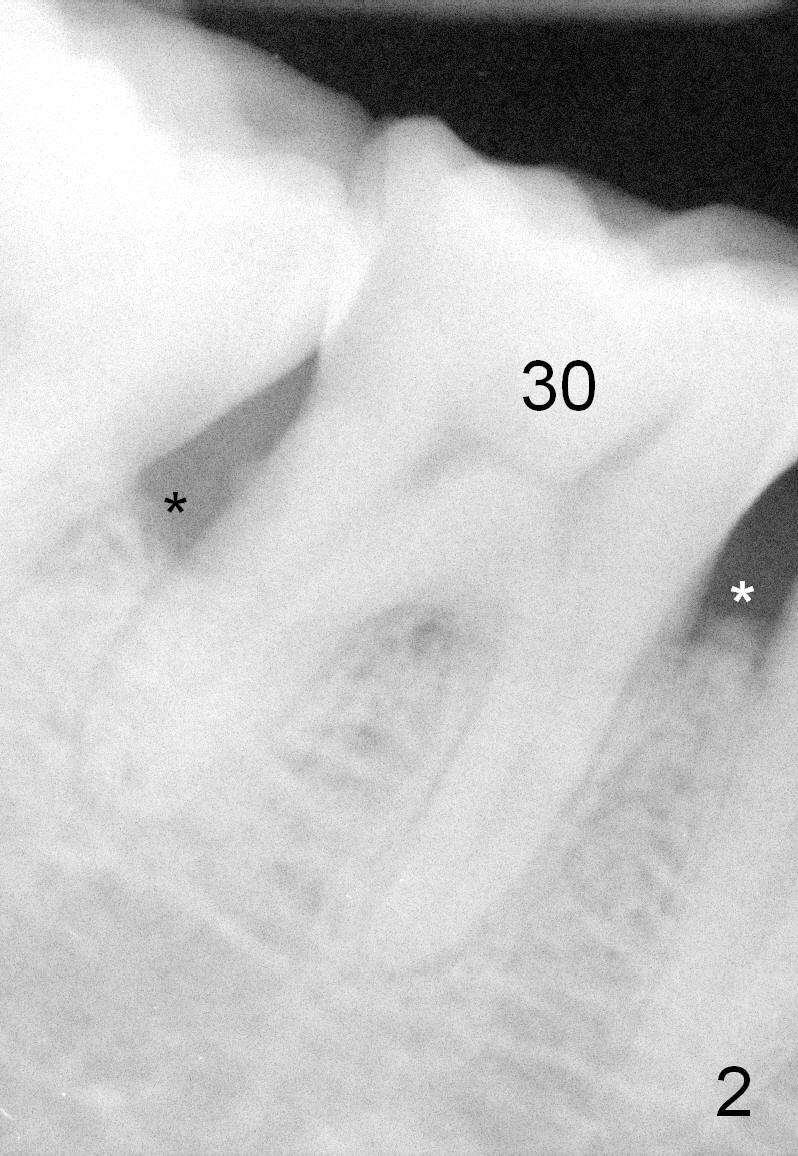

One year and a half years ago, the tooth #31 of a 48-year-old man had infection (Fig.1 *) and was extracted without implant. There was more bone loss in the distal of #30 than in the mesial (Fig.2 *). Recently the patient returns with infection at #30 distally with severe bone loss (Fig.3 *). An immediate implant is to be placed mainly in the mesial socket (Fig.4 (bone-level), Fig.5 (tissue-level)).